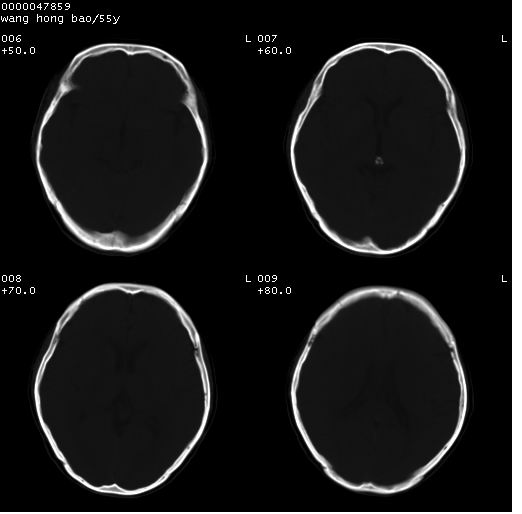

以下是引用dyqct在2008-5-3 23:36:00的发言:[br]桥前池区可疑蛛网膜囊肿。其它未见明显异常。建议做mri。

以下是引用qiushi在2008-5-4 10:10:00的发言:[br]鞍上池前缘突出影为双侧额叶直回;箭头所指为双侧正常之人字缝.[br]桥前池区可疑表皮样囊肿或蛛网膜囊肿,必要时mri

以下是引用zjzjr在2008-5-4 14:50:00的发言:[br]桥前池区可疑蛛网膜囊肿。其它未见明显异常。建议做mri。